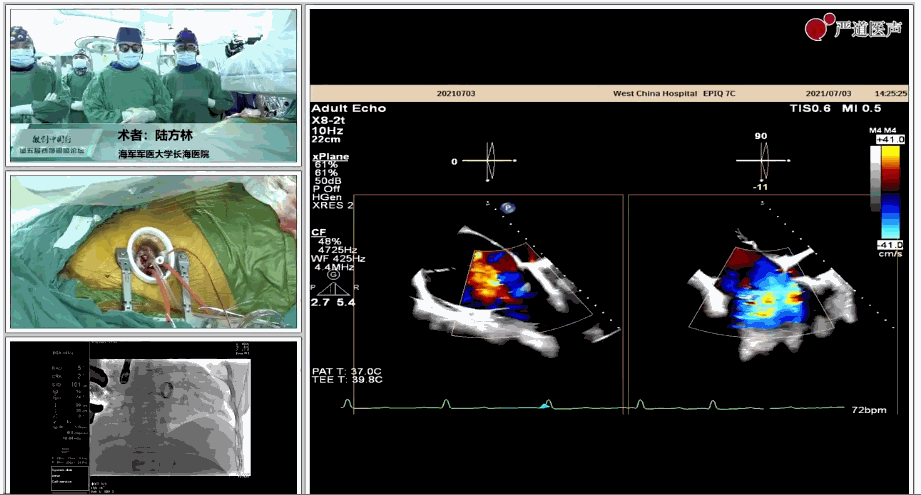

7月3日下午,海軍軍醫大學附屬上海長海醫院心血管外科徐志云、陸方林團隊在論壇中分享了經導管三尖瓣置換術(LuX-Valve®)的手術直播演示。線下會議由陶涼教授、潘文志教授、喬晨暉教授共同參與討論和臨床分享。

陸方林教授分享的是一例極重度三尖瓣返流的患者采用健世科技(LuX-Valve®)經導管三尖瓣置換系統進行的手術直播演示。此例患者為69歲女性,入院前17年行二尖瓣機械瓣置換術,術后長期服用華法林抗凝,既往“2型糖尿病”病史5年,“雙下肢水腫”3年。3個月前患者出現腹脹、雙下肢水腫,伴活動后暈厥,伴黃疽、皮膚濕癢、牙齦出血,癥狀持續加重,遂入院治療。入院后行心臟CT、心臟超聲檢查,提示:“三尖瓣關閉不全(極重度),二尖瓣置換術后,心功能III級”。徐志云、陸方林微創三尖瓣置換團隊對該患者的病情進行了充分的評估和討論。由于患者有開胸二尖瓣置換手術史,且病史時間長,同時存在相關合并癥,傳統外科手術風險極高(STS評分:8.315%),最終決定采用三尖瓣LuX-Valve®瓣膜系統對患者進行治療。

▲術中食道超聲顯示三尖瓣極重度返流